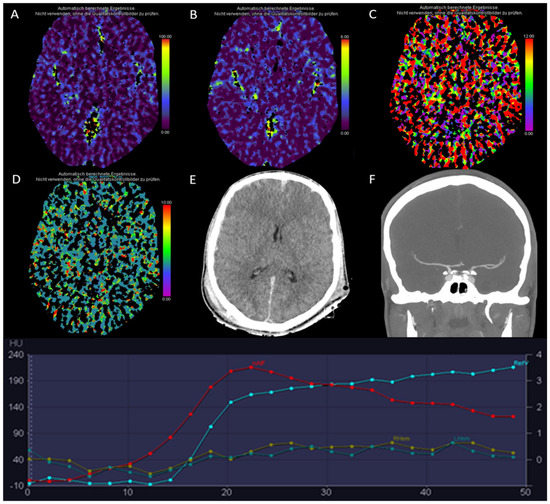

3.11. Technical Pitfalls